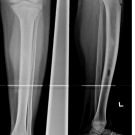

A 15-year-old boy presented with persistent pain in the mid left leg for the past 3 weeks. The pain was associated with a limp and sometimes awoke him from sleep.